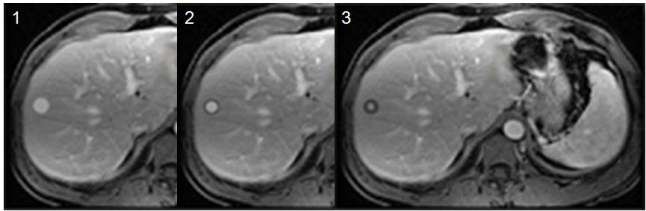

SIGNO DEL LAVADO PERIFÉRICO

Signo de nódulo hepático maligno en Resonancia Magnética con contraste (gadolinio). La periferia del nódulo muestra un aclaramiento del contraste más rápido que el centro. Este hallazgo, no visto en lesiones benignas, guarda relación con la vascularización del tumor, mayor en la periferia, por ser la zona de crecimiento tumoral.

Es un signo poco sensible pero muy específico: 100 %. Se ha descrito en metástasis de tumor carcinoide y cánceres de mama, colon y estómago. El signo es más visible a los 10 minutos tras la administración de contraste.

Las imágenes corresponden a una simulación de lesión metastásica hepática en una secuencia de imágenes de RM tras la administración de contraste (gadolinio). Imágenes potenciadas en T1. Imagen 1: imagen obtenida precozmente en el que la lesión capta contraste de manera uniforme. Imagen 2: en una fase más tardía la periferia de la lesión va disminuyendo su brillo debido al lavado del contraste. Imagen 3: corte tardío en el que sólo una pequeña zona central de la lesión mantiene el realce por el contraste.

Para saber más puedes consultar: Mahfouz H-E y cols. Peripheral washout: a sign of malignancy on dynamic gadolinium-enhanced MR images of focal liver lesions. Radiology 1994; 190:49-52.